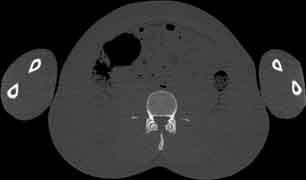

Visible Human male: Sectio transversalis 1702

NMR

Pd                          / T2 \                         T1